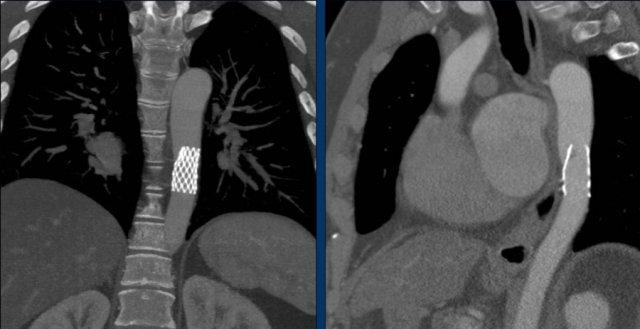

TAVR

TAVR là thay van động mạch chủ qua đường ống thông (transcatheter aortic valve repair).

Van động mạch chủ bị hẹp được sửa chữa bằng cách đặt van nhân tạo vào bên trong van bệnh lý.

TAVR dành cho những bệnh nhân có nguy cơ cao khi thực hiện phẫu thuật mở.

Tỷ lệ thành công của thủ thuật là 90%.

TAVR có liên quan đến tỷ lệ cao hơn về tổn thương mạch máu, hở cạnh van và nhu cầu đặt máy tạo nhịp tim vĩnh viễn.